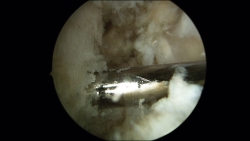

Una vez realizados los 2 túneles, desde el portal anterolateral se inserta el tornillo de biotenodesis de 5 × 15 mm con la plastia colocada hasta la punta del destornillador y se inserta el tornillo siguiendo la técnica (Figura 6).

Figura 6. Tornillo de biotenodesis con la plastia colocada y lista para su introducción.

Posteriormente, desde el portal accesorio, con la ayuda de un pasahilos, se pasan los hilos del extremo distal de la plastia a través del pequeño túnel que ha dejado la aguja guía que hemos utilizado para hacer el túnel del astrágalo; de esta manera introducimos la plastia en el túnel del astrágalo y le podemos dar la tensión adecuada en el momento de colocar el tornillo (Figura 7).

El segundo tornillo interferencial de 5 × 15 mm se coloca desde el portal accesorio, con el tobillo en valgo y en neutro de flexoextensión, mientras traccionamos de la sutura para dar la tensión adecuada a la plastia.